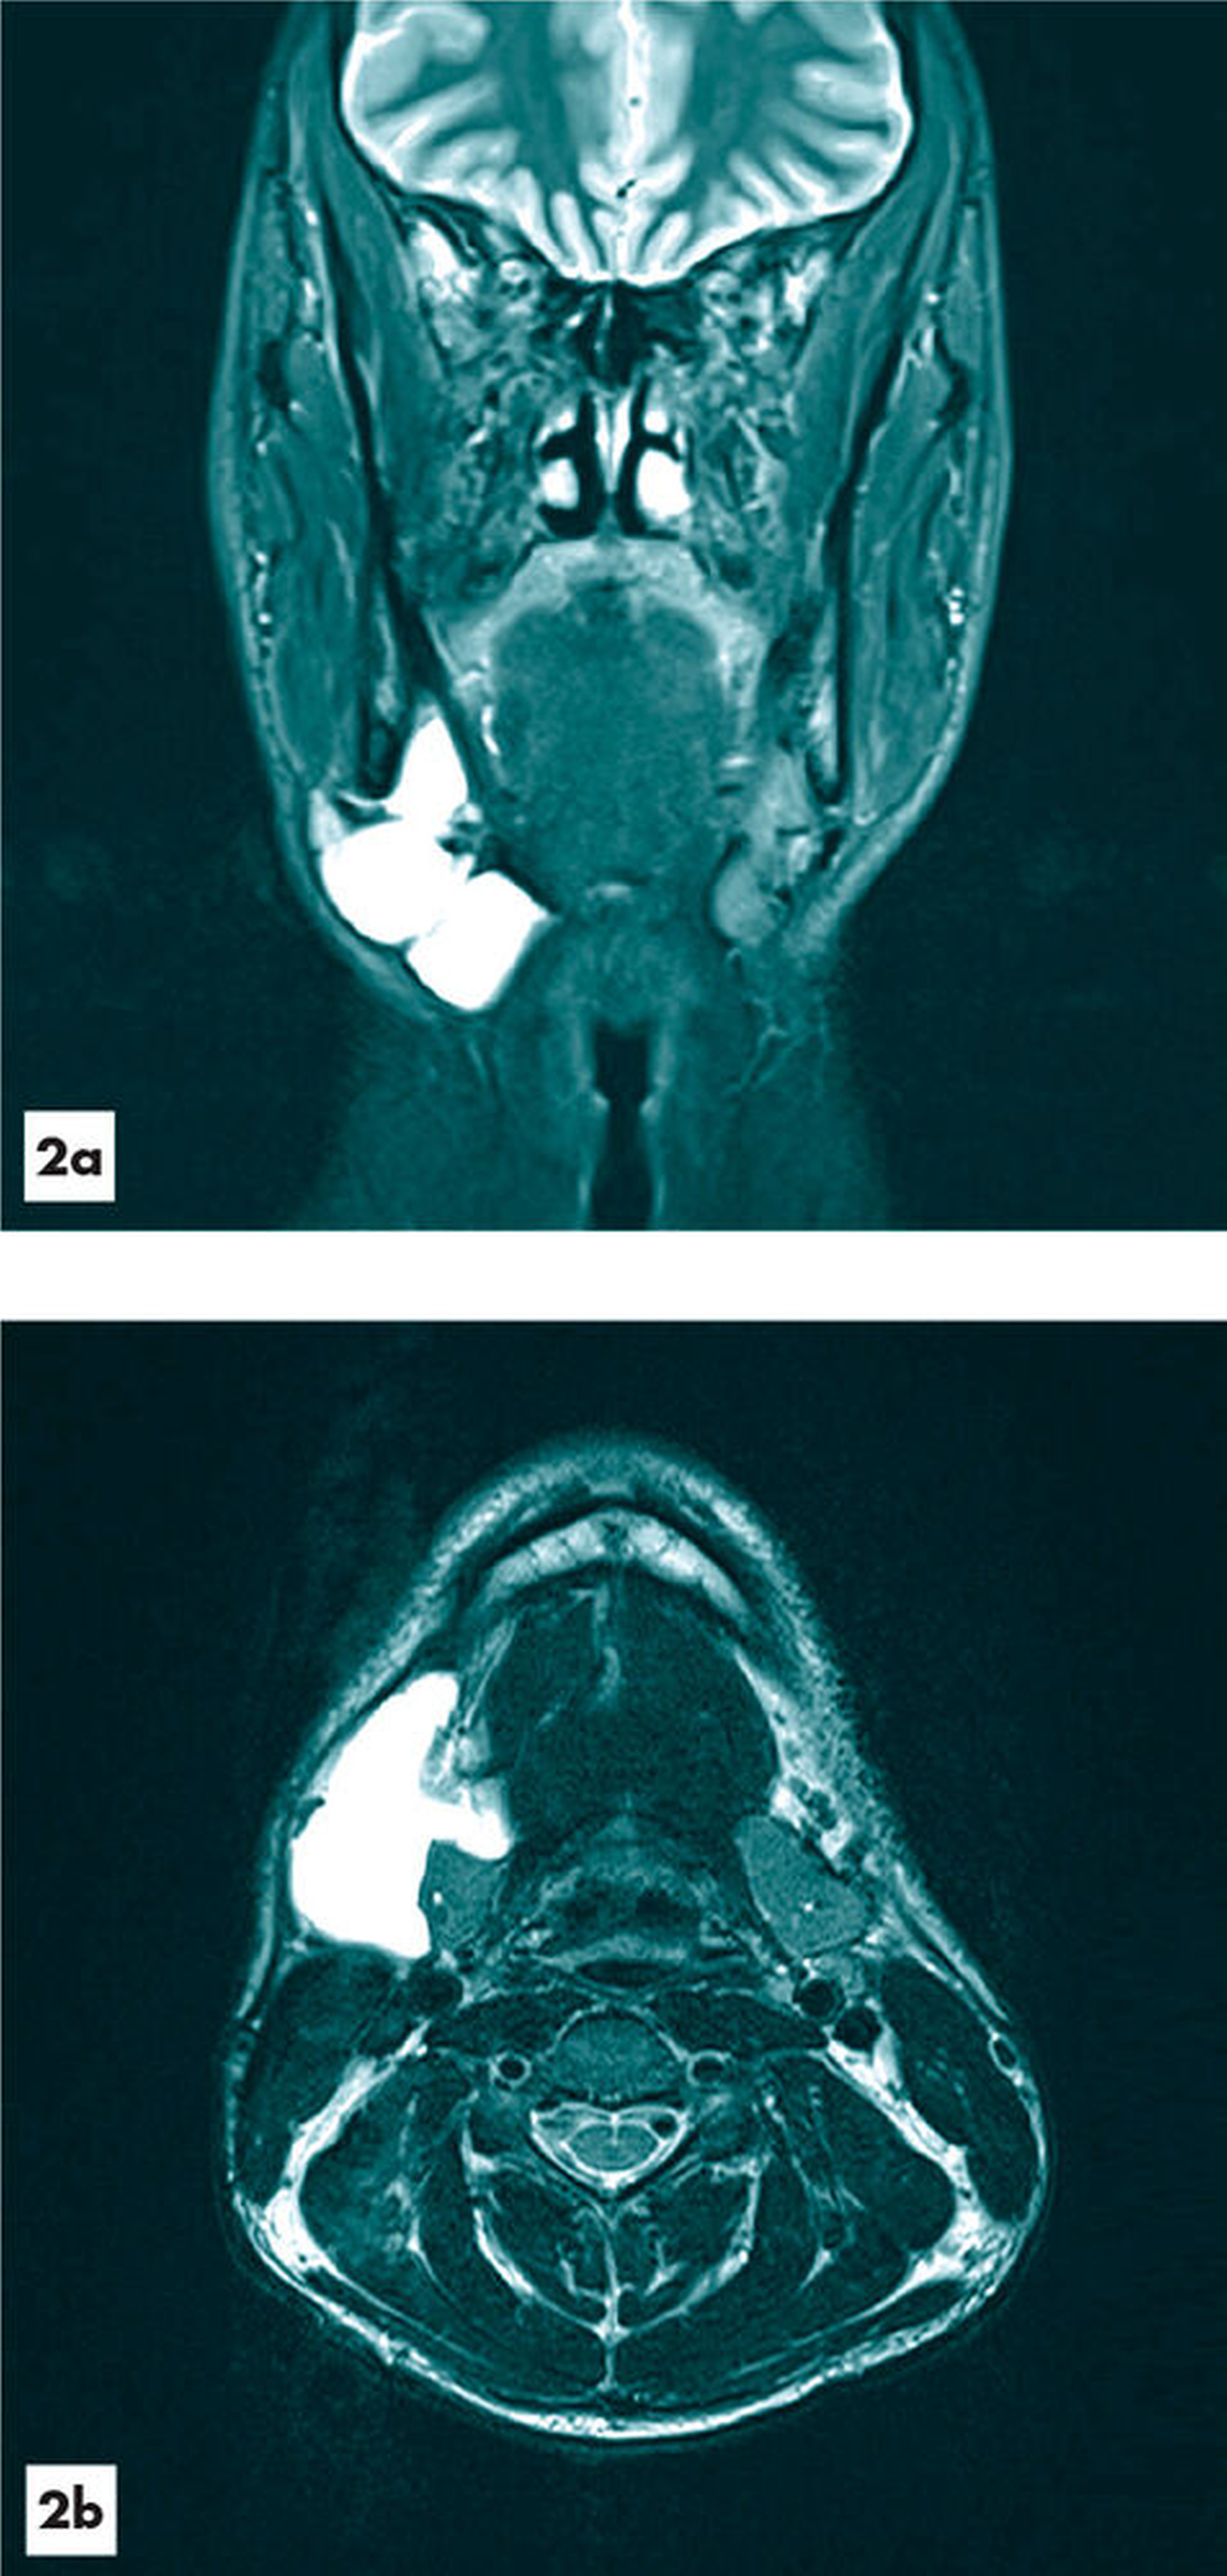

Im Jahr 2016 suchte der Patient einen niedergelassenen HNO-Kollegen wegen Schmerzen im Bereich der zervikalen Schwellung und eines neu aufgetretenen Lagerungsschwindels auf. Bei der daraufhin veranlassten MRT-Untersuchung wurde von radiologischer Seite erstmals der Verdacht auf eine Tauchranula geäußert (Abbildung 2). Jedoch wurden diesbezüglich keine weiteren Therapieschritte unternommen. Aufgrund der Persistenz der Schwellung suchte der Patient in der Folgezeit mehrere Kliniken auf, wobei die klinischen, sonografischen und radiologischen Befunde zunächst für das Vorliegen einer lymphatischen Malformation sprachen.

Die Magnetresonanztomografie ist die sensitivste Methode zur Diagnostik einer Tauchranula, wobei insbesondere in der T2-Wichtung aufgrund des Flüssigkeitsgehalts von einer hohen Signalintensität des Befunds ausgegangen werden kann. Differenzialdiagnostisch können lymphatische Malformationen, Ductus-thyreoglossus-Zysten, Lipome, Dermoidzysten, weitere vaskuläre Malformationen oder entzündliche veränderte Lymphknoten in Betracht gezogen werden [AlHayek et al., 2018; Gupta und Karjodkar, 2011]. Auch eine maligne – wenngleich auch sehr seltene – Entartung zu einem oralen Plattenepithelkarzinom wurde beschrieben [Ali et al., 1990].